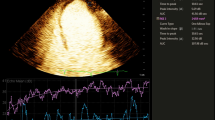

Comparison of myocardial blood flow (MBF) in the infarct and non infarct region. a Late gadolinium enhancement image showing scar and microvascular obstruction area (highlighted in yellow) in the inferior and inferolateral region. b First pass perfusion image showing segmentation of a short axis slice into 6 segments. c Myocardial (green and white) and blood pool (red) signal intensity versus time curves at stress. Stress infarct region MBF (white) is lower than the stress non infarct region MBF. d Signal intensity versus time curves at rest. The MBF at rest is lower than at stress. Resting infarct region MBF (white) is lower than the resting non infarct region MBF (green)

For perfusion analysis to quantify resting and stress infarct region MBF, we used the methodology as previously described [15]. In brief, the endocardial and epicardial contours of three short axis sections (base, mid and apex) were traced (MASS version 7.2, Medical Imaging Solutions, Leiden, the Netherlands) and corrected manually for displacements (e.g. breathing) by an examiner blinded to coronary angiography findings. In each short axis slice, MBF was determined for 6 myocardial segments in ml min−1 g−1 by deconvolution of signal intensity curves with an arterial input function measured in the left ventricular blood pool, with explicit accounting for any delay in the arrival of the tracer (Fig. 1). As basal MBF is closely related to the rate-pressure product, an index of left ventricular oxygen consumption, values for basal flow in each patient were also corrected for the respective rate-pressure product (i.e, the absolute values of flow were divided by rate-pressure product/10,000) [15]. Segments were assigned to vascular regions according to the segmental model of the American Society of Echocardiography, with modifications to correct for variable coronary dominances as previously described [25]. Segments 6, 1 and 2 were assigned to the left anterior descending artery; segments 2, 3 and 4 were assigned to the circumflex artery; and segments 4 and 5 were assigned to the right coronary artery (Fig. 2). The MBF in the infarct region at stress and at rest was determined, termed ‘stress infarct region MBF’ and ‘resting infarct region MBF’. The difference between stress infarct region MBF and resting infarct region MBF was calculated and termed ‘infarct region MBF difference’.